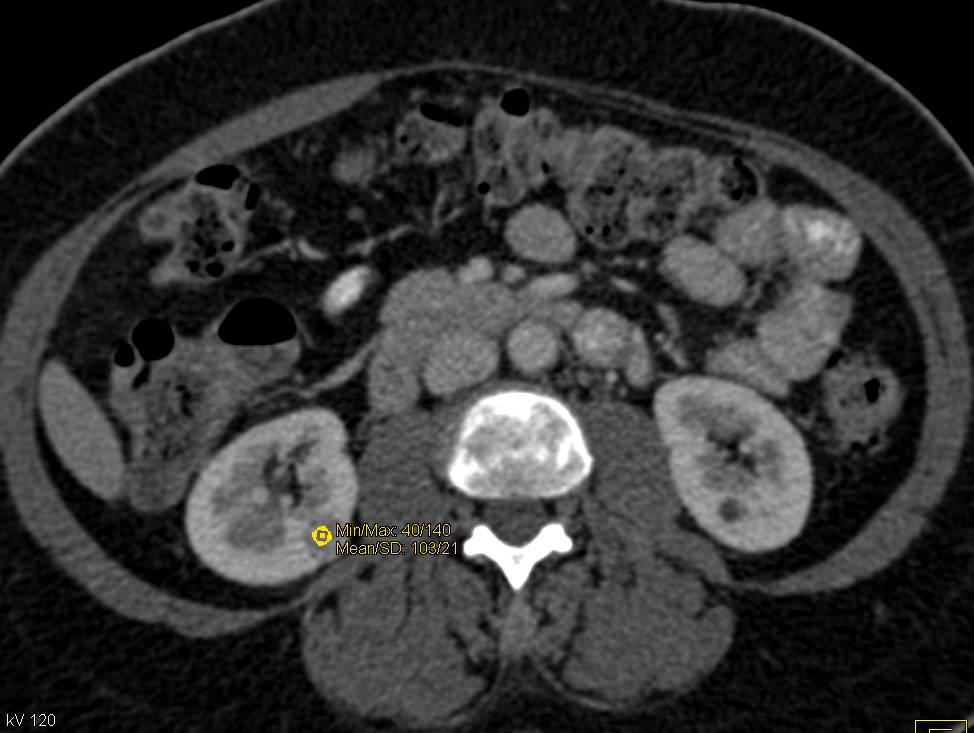

Metastatic Renal Cell Carcinoma to the Contralateral Adrenal Gland